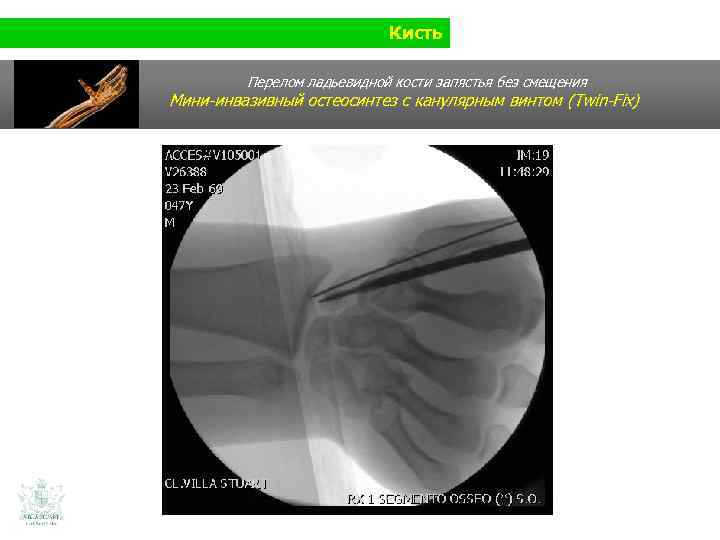

Кисть Клинический случай (кисть) Мужчина 35 лет Падение на ладонь (при защитной реакции)

Кисть Перелом ладьевидной кости запястья без смещения

Кисть Перелом ладьевидной кости запястья без смещения Мини-инвазивный остеосинтез с канулярным винтом (Twin-Fix)